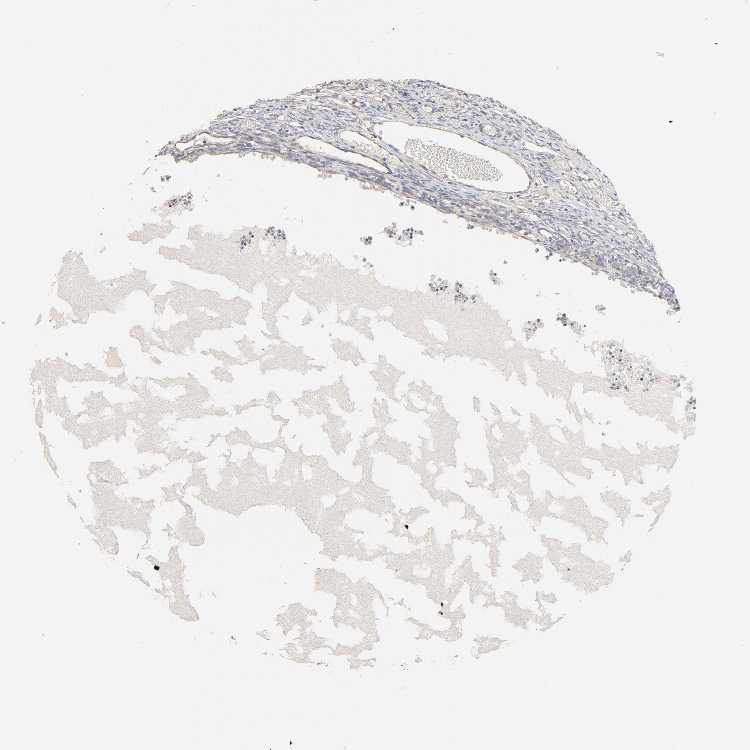

OVARY - Antibody stainingi

Antibody staining in the annotated cell types in the current human tissue is reported as not detected, low, medium, or high, based on conventional immunohistochemistry profiling in selected tissues. This score is based on the combination of the staining intensity and fraction of stained cells.

Each image is clickable and will lead to virtual microscopy that enables deeper exploration of all samples and also displays staining intensity scores, fraction scores and subcellular localization as well as patient and tissue information for each sample.

Antibody HPA000962Antibody HPA004119

Follicle cells Not detected-

Ovarian stroma cells Not detectedLow